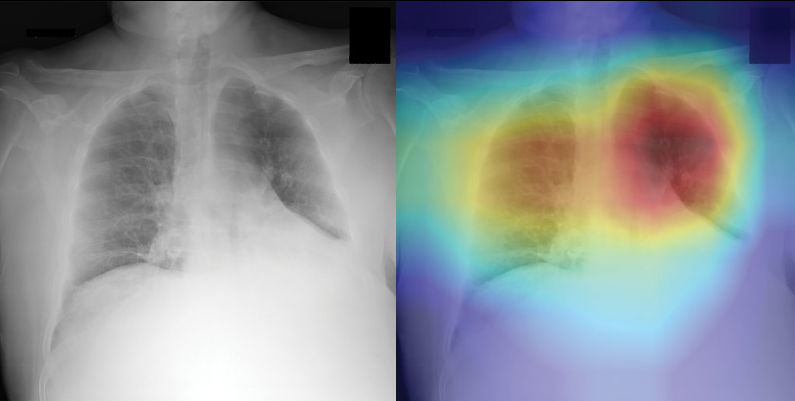

UW Uses AI to Help Diagnose COVID Pneumonia on Chest Radiography

Ran Zhang, PhD, and his collaborators were the first group to publish work on the implementation of AI in diagnosing COVID pneumonia.